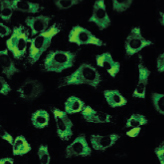

과학적으로 입증된 한약 치료 효과, 더 이상의 퇴행을 막아 노후 삶의 질을 높여드립니다.

연골 보호 및 재생

신경 재생